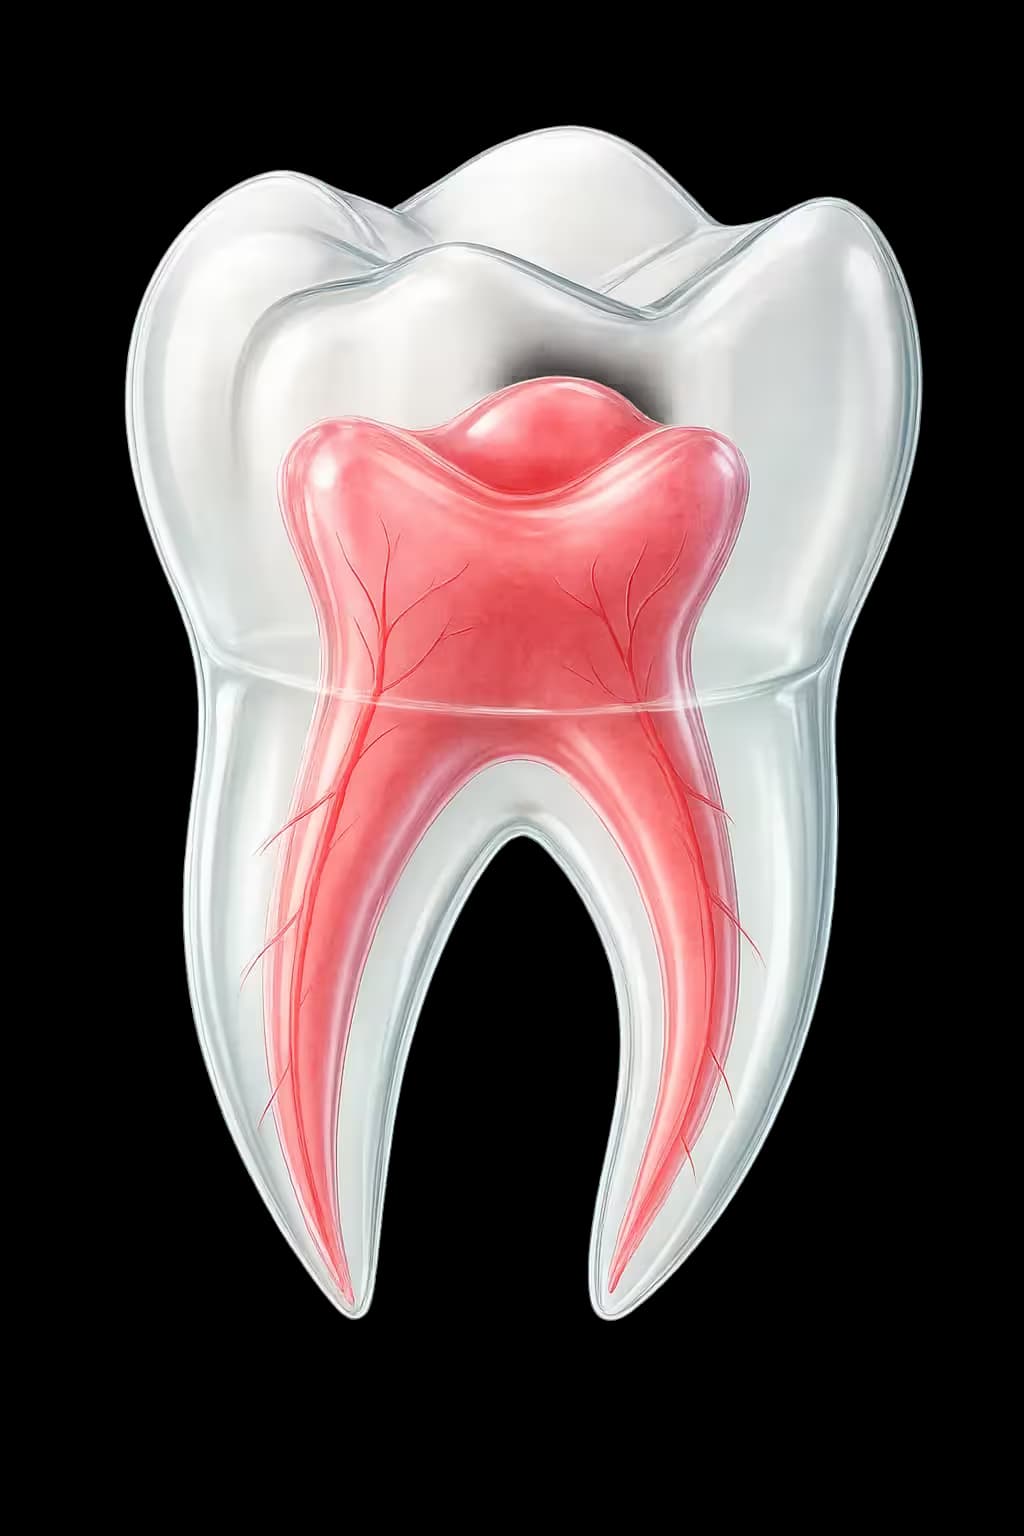

Advanced diagnostic technologies